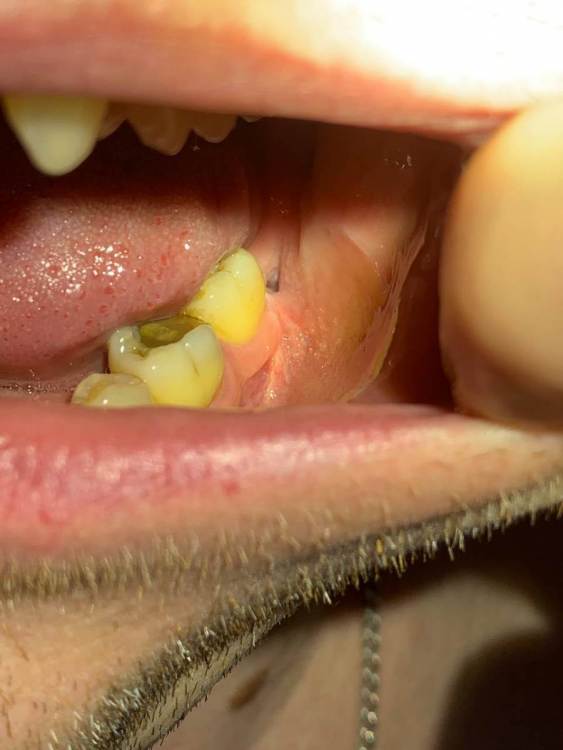

3убастик Опубликовано 9 июня, 2023 Автор Поделиться Опубликовано 9 июня, 2023 27.05.2023 в 21:28, Irouil сказал: Нормально Поделал по вашей схеме. Завтра утром будет как 2 недели закладывал 2 раза в день на 15 минут метрогил, промывал раза 3 после еды хлоргексидином, сейчас лунка выглядит таким образом. Есть чувствительность к горячему\холодному. Подскажите, это нормальное состояние? И белый налёт внутри это фибрин? Что можно еще поделать чтобы поскорей зажило, метрогил я так понимаю уже не стоит продолжать, как и хлоргексидин. Ссылка на комментарий

Irouil Опубликовано 10 июня, 2023 Поделиться Опубликовано 10 июня, 2023 Я полагаю Вам пора сделать свежий снимок и сходить на осмотр, прошло уже практически два месяца с удаления (если мои подсчеты верны), для этого срока выглядит не прекрасно чувстуительность скорее всего от соседнего зуба Ссылка на комментарий

3убастик Опубликовано 10 июня, 2023 Автор Поделиться Опубликовано 10 июня, 2023 1 час назад, Irouil сказал: Я полагаю Вам пора сделать свежий снимок и сходить на осмотр, прошло уже практически два месяца с удаления (если мои подсчеты верны), для этого срока выглядит не прекрасно Через 9 дней будет 2 месяца ровно. Ссылка на комментарий

3убастик Опубликовано 12 июня, 2023 Автор Поделиться Опубликовано 12 июня, 2023 Сходил я к хирургу, он посмотрел и сказал что всё нормально и лунка эпителизирована, но на дне лунки красное, это не похоже на эпителий. И именно лунка реагирует на холодное, горячее, соленое и сладкое, а не 7ка, она в полном порядке. Сказал просто полоскать после еды ромашкой, или холисал закладывать 3 раза в день. Купил холисал, при закладке ватной палочкой в лунку тоже больно, как и от холодного\горячего, 7ки даже не касаюсь, боль идёт явно из лунки. Скажите, может ли в лунке остаться мелкая пыль от зуба, или что-то в этом роде, которую не видно на снимке и не давать зажить? Ссылка на комментарий